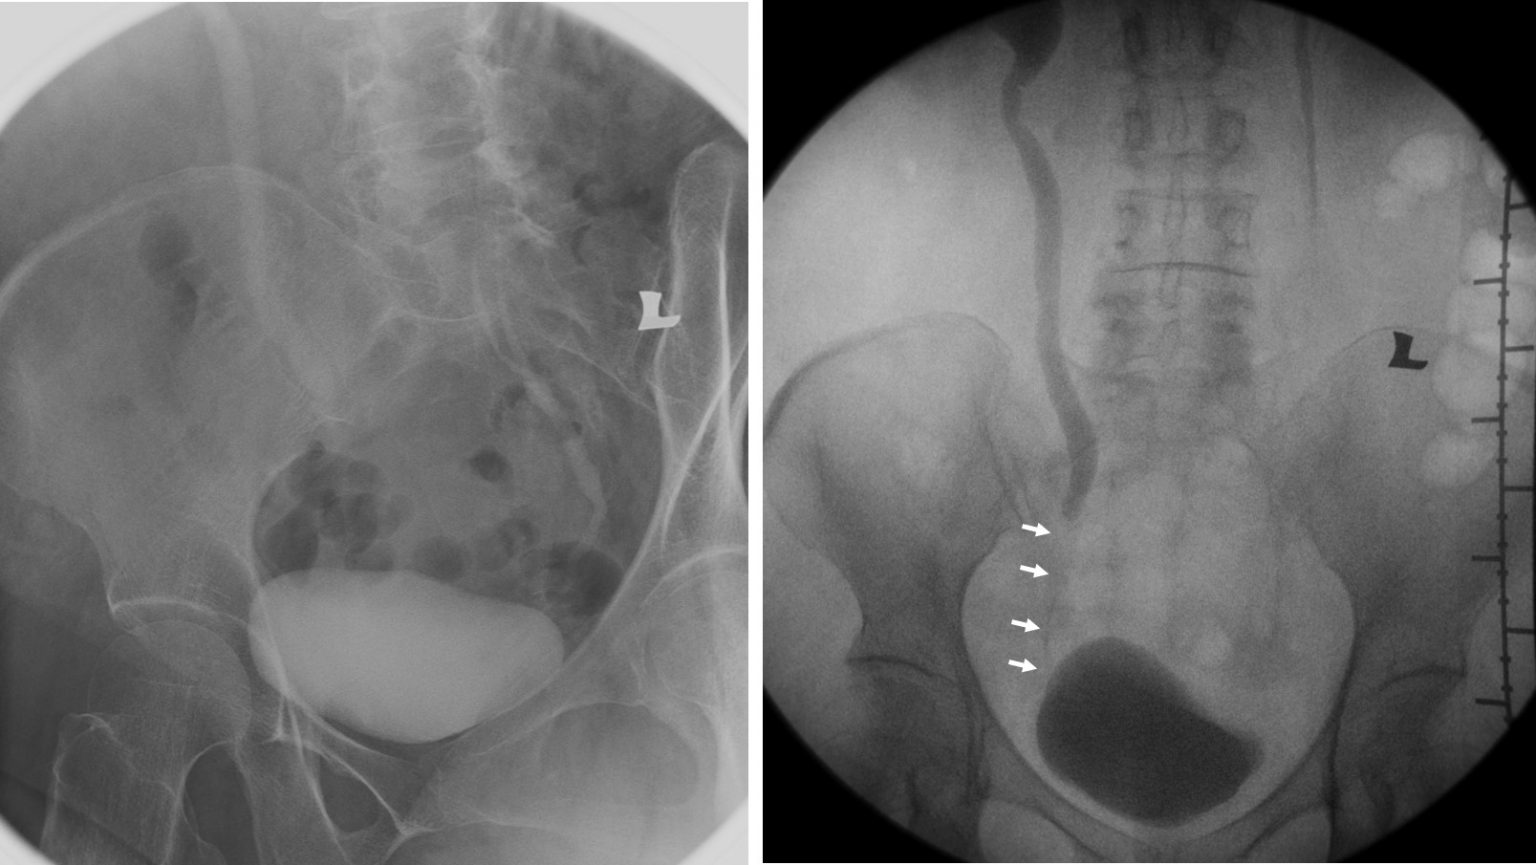

Adult ureteral stricture and duplex system of contralateral side

Radiopaque calculi (arrows) inside urinary bladder Download No Radiopaque Calculus approximately 90% of calculi are radiopaque on radiographs whereas almost all stones are radiopaque on. Secondary signs of renal colic may be seen on radiography. urolithiasis is a common clinical entity. approximately 90% of urinary tract calculi are radiopaque. less radiopaque calculi, such as pure uric acid stones and stones composed mainly of cystine or magnesium. No Radiopaque Calculus.